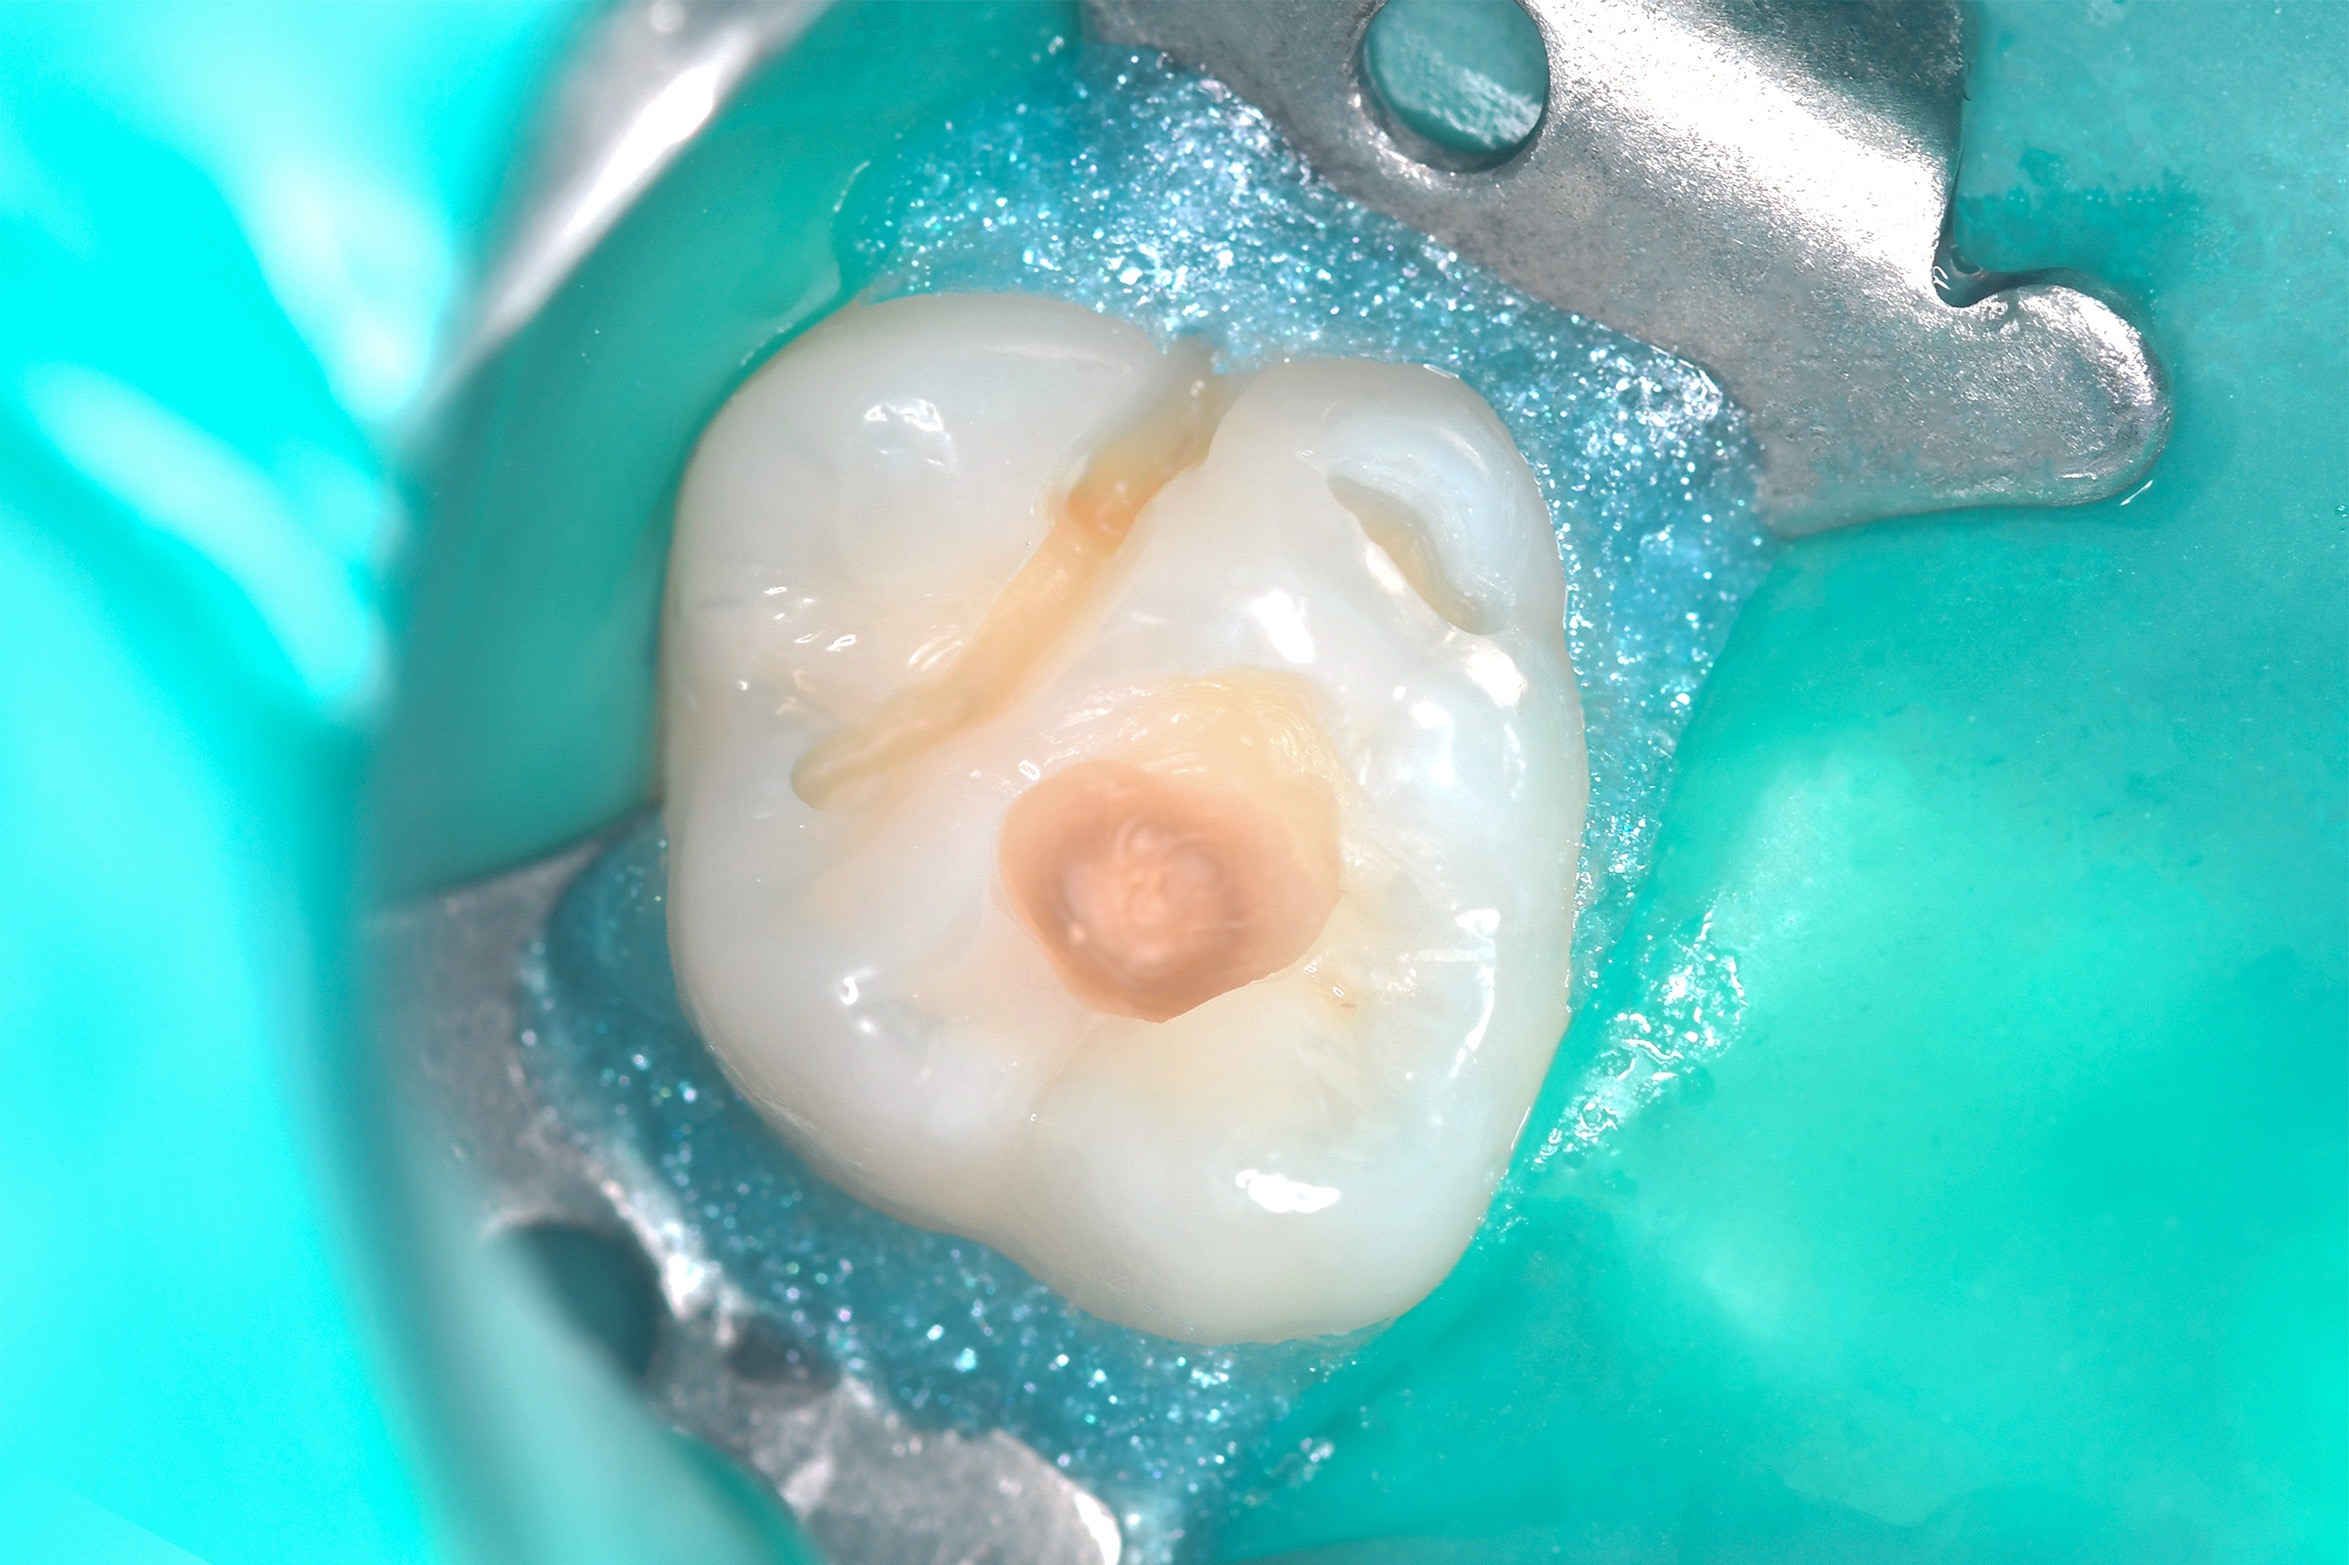

Пациентка 11 лет, жалоб на боль нет, при проведении профессиональной гигиены выявлен кариес на постоянном 16 зубе.

Лечение кариеса постоянного 16 зуба